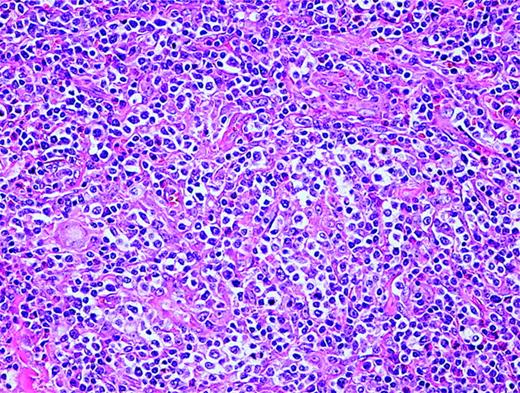

Anaplastic large-cell lymphoma. Infiltrate is composed of large transformed lymphocytes, including hallmark cells with kidney-shaped nuclei.

The morphology of ALCL, systemic type, consists of large lymphoid cells with pleomorphic or multiple prominent nuclei and abundant cytoplasm (Figure 3). Tumor cells grow in a cohesive pattern, and there is often sinusoidal spread in the lymph nodes. Tumor cells express CD30 and either T cell or no specific lineage antigens (null cell).